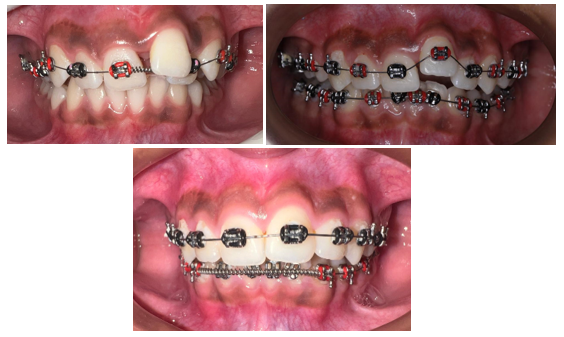

Male patient 11 years old with permanent dentition, skeletal class II, straight profile, compressed airway, cervical bone maturation stage CS2, presents compression of the upper arch and deep palate, mandibular retrogantism, with an upper model discrepancy -7.5mm, Bolton analysis shows anterior discrepancy of 5.4mm, the Pont analysis shows a transverse length deficit of -9.20mm, severe crowding in the upper jaw, moderate crowding in the lower jaw, facial biotype is mild Dolicofacial, in the periodontal examination aberrant lingual and labial frenulum was observed; the lower one limits the lingual movement. The indicated examinations included: intraoral photography, panoramic and lateral skull radiographs. When evaluating the results it was corroborated the existence of a transverse micrognathism of the maxilla (Figure 1).

Figure 1.